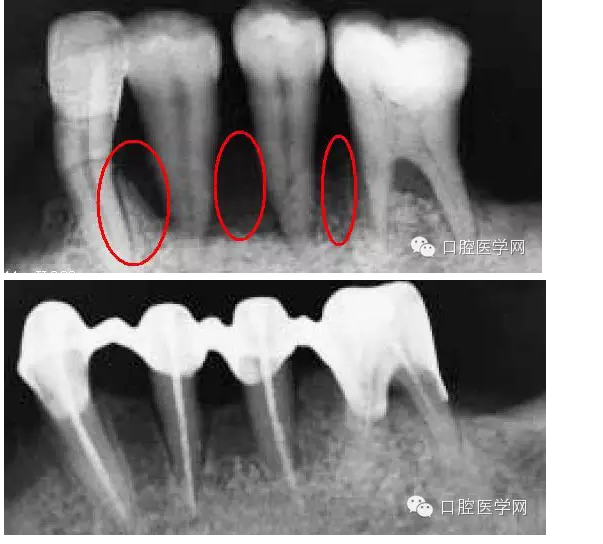

接上面的照片發(fā)一張X-RAY,從圖片中大家應(yīng)該能看到,骨已經(jīng)吸收了,所以骨喪失是牙齦乳頭吸收最主要的原因——牙周區(qū)的紅色美感是依靠骨來支持。

但是,并不是所有的牙齦退縮都是無法在恢復(fù)的。一些患者在去除刺激物包括炎癥,骨是可以基本恢復(fù)原來的健康的(或者說恢復(fù)一些)。當(dāng)然你要通過X-RAY分辨出骨的吸收情況是什么樣。如果象上面第一個(gè)病例那張X-RAY那樣,水平吸收嚴(yán)重就別想了。但如果是下圖這樣,牙齒周圍還保留有骨壁,只要去除炎癥、不良修復(fù)體和調(diào)整咬合情況,骨是可以恢復(fù)的。所以,齦乳頭黑三角最好拍張X-RAY去看看骨的情況,而醫(yī)生不只是對(duì)牙周,同時(shí)對(duì)其他學(xué)科也應(yīng)該有些了解。